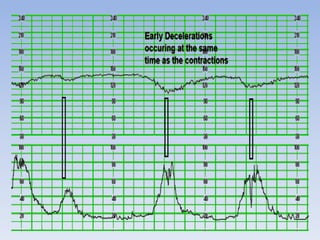

– Early Decelerations

• uniform, repetitive decrease of FHR with slow onset early

in the contraction and slow return to baseline by the end of

the contraction

Early decelerations

• Gradual decrease in FHR

with onset of deceleration to

nadir >30 seconds.

• The nadir occurs with

the peak of a contraction.

Early decelerations • Gradualdecrease in FHR with onset of deceleration to nadir >30 seconds. • The nadir occurs with the peak of a contraction.